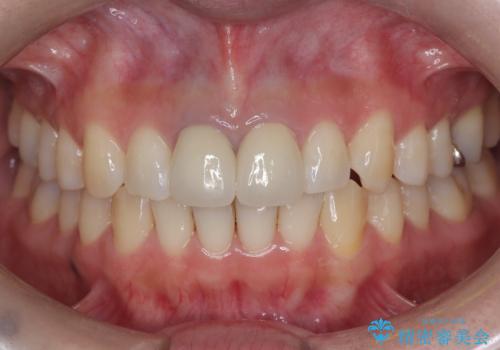

セラミッククラウンで前歯の変色を改善

セラミッククラウンによって前歯の変色が改善され、また歯の形も希望の形態へ修正しました。